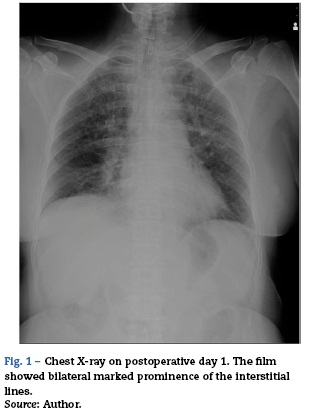

Saturation of peripheral oxygen (SpO2) and end-tidal carbon dioxide concentration (ETCO2) were also continuously monitored. The operation time for the procedures was 99 min. Fluid balance was 1290 ml. No transfusion was performed. During the operation, the patient's haemodynamics were stable with blood pressure of around 120/80 mmHg and 3.5-IL/min of cardiac output. Respiratory condition was also stable; however, SpO2 was slightly decreased as the end of operation neared. Immediately after the operation, she was returned to the supine position and her trachea was suctioned; however, only a small amount of frothy sputum was observed. Simultaneously, she regained consciousness and spontaneous breathing was sufficient, then the tracheal tube was removed and she was transferred to the intensive care unit (ICU). After admission to the ICU, she remained alert and neuro-logically unchanged. Oxygen was administered by facemask at 6Lmin-1; however, her SpO2 showed 90-96% and PaO2 was 89 torr with deep breathing urged. She never complained of dyspnoea no matter how many times we asked although she were coughing up and spitting out. Her haemodynamics was stable throughout the ICU stay. Transthoracic echocardiogram showed normal left ventricular function and normal chamber size. On the next day, her bladder temperature was 37.1 °C. Inflammatory markers, such as C-reactive protein (CRP) and white blood cell (WBC) counts, were 1.3 mg/dl and 11,000/[xl with prophylactic administration of cefazolin 2 g/day for surgical site infection. Presentation of active pneumonia seemed negative. However, a chest X-ray taken on that day, which showed bilateral marked prominence of the interstitial lines, were consistent with pulmonary oedema (Fig. 1). A subsequent CT exam, which demonstrated inter- and intralobar septal lines some peribronchial cuffing and ground-glass areas, confirmed the diagnosis of pulmonary oedema (Fig. 2).

She was still monitored closely in the ICU according to the institutional standard care for neurosurgical patients but was observed only with oxygen administration. Diuretics or any specific therapies were not applied. Gradually, bilateral interstitial lines in the chest X-rays spontaneously disappeared (Fig. 3). On the 5th postoperative day, she was finally weaned from oxygen therapy.